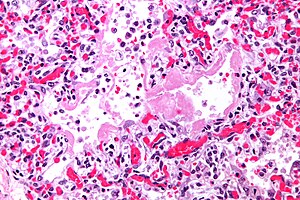

Micrograph of diffuse alveolar damage, the histologic correlate of acute interstitial pneumonitis. H&E stain.

Rapid progression from initial symptoms to respiratory failure is a key feature. An X-ray that shows ARDS is necessary for diagnosis (fluid in the small air sacs (alveoli) in both lungs). In addition, a biopsy of the lung that shows organizing diffuse alveolar damage is required for diagnosis. This type of alveolar damage can be attributed to nonconcentrated and nonlocalized alveoli damage, marked alveolar septal edema with inflammatory cell infiltration, fibroblast proliferation, occasional hyaline membranes, and thickening of the alveolar walls. The septa are lined with atypical, hyperplastic type II pneumocytes, thus leading to the collapse of airspaces. Other diagnostic tests are useful in excluding other similar conditions, but history, X-ray, and biopsy are essential. These other tests may include basic blood work, blood cultures, and bronchoalveolar lavage.[citation needed] The clinical picture is similar to ARDS, but AIP differs from ARDS in that the cause for AIP is not known.